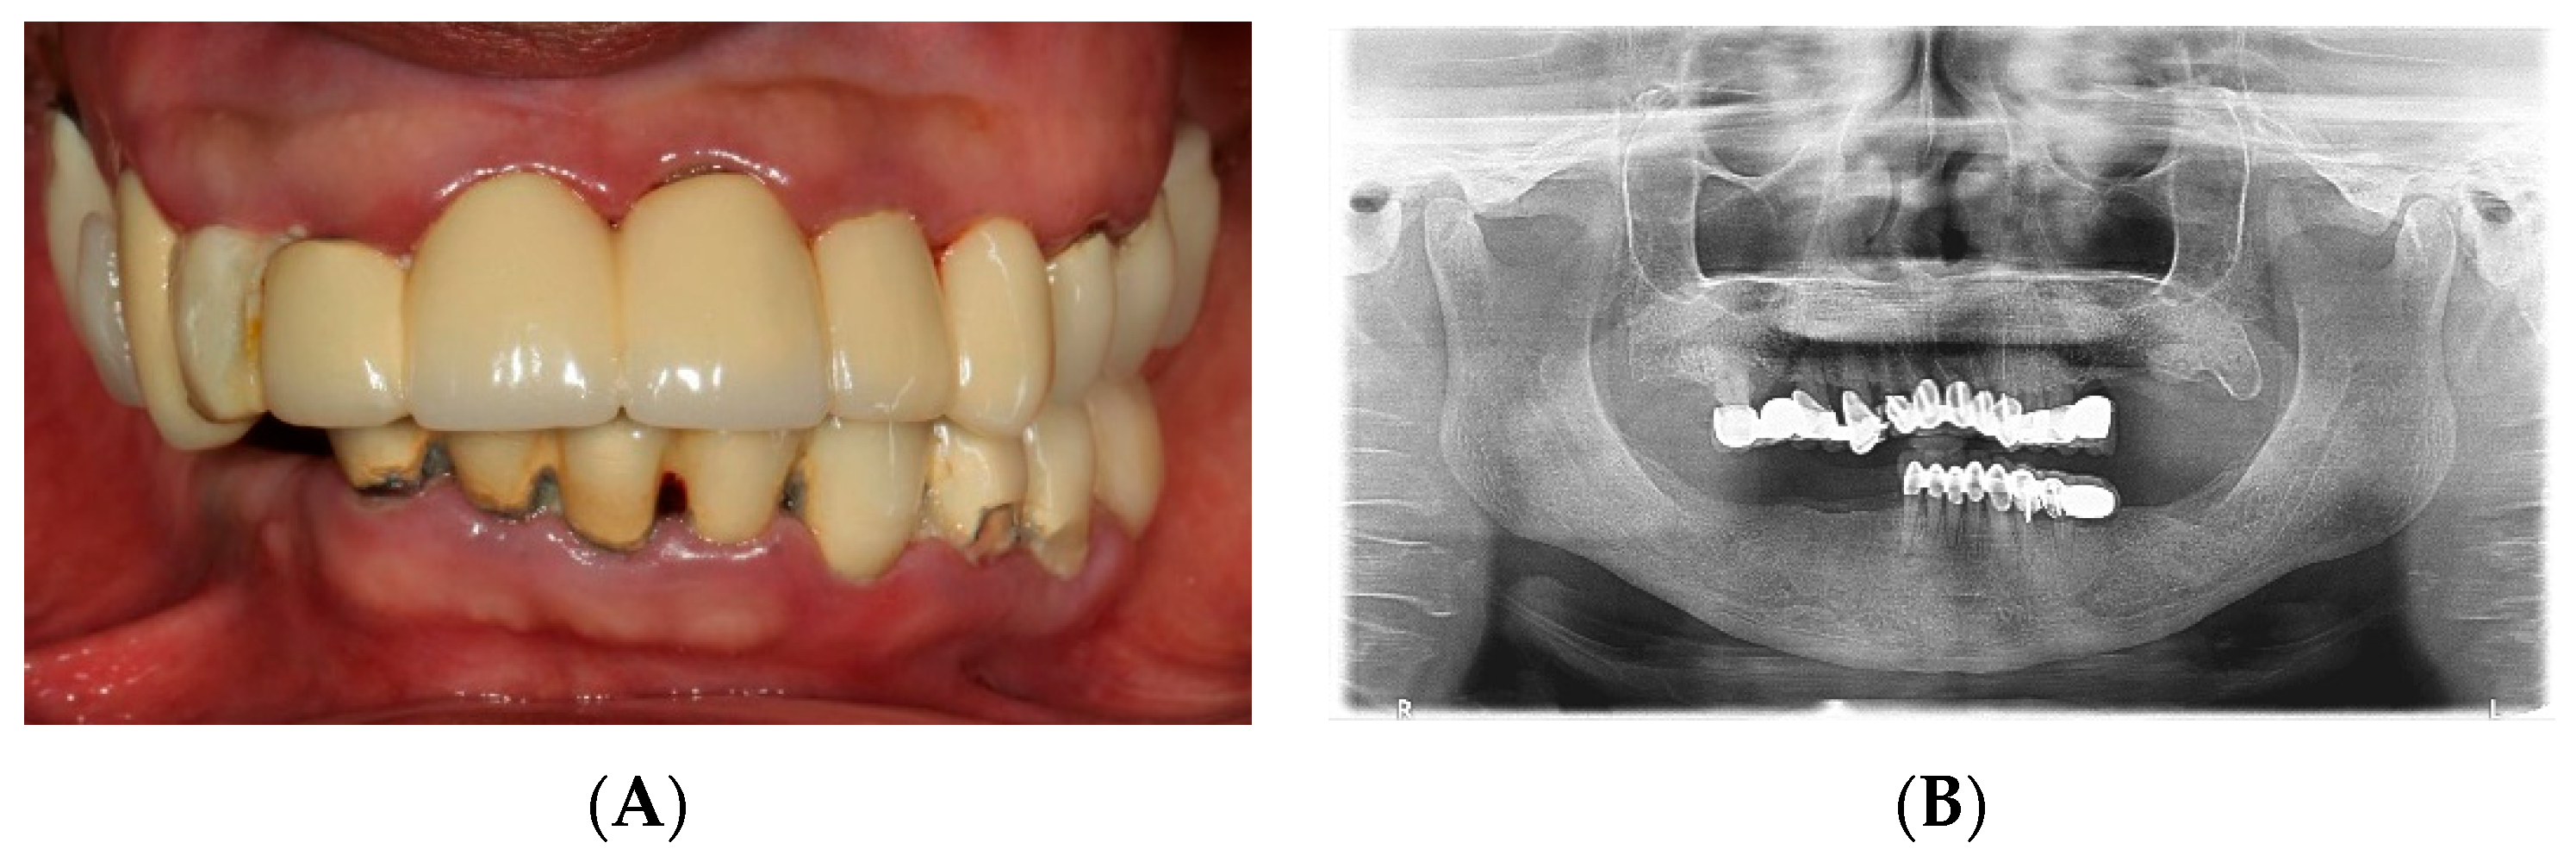

2.1. Diagnostic Phase

2.2. Foundational Phase: Elimination of Active Disease, Extraction and Fixed Provisional Prosthesis